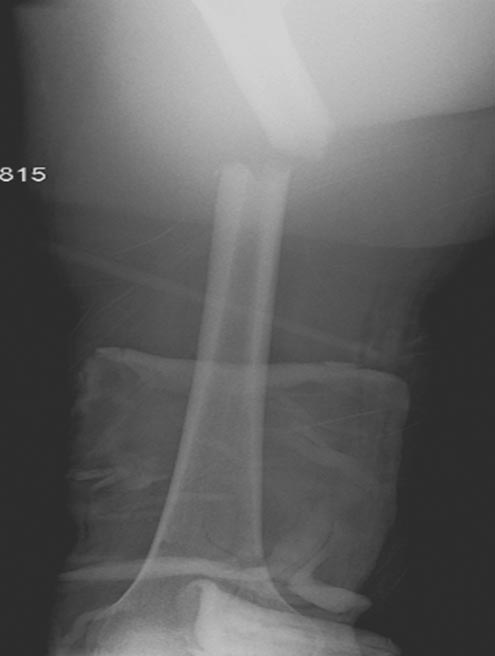

[Ortho] Polytrauma

Вложение не в текстовом формате было извлечено…

Имя     : Picture1.jpg

Тип     : image/jpeg

Размер  : 70367 байтов

Url     : http://weborto.net:8080/pipermail/ortho/attachments/20180407/cb9d5034/attachment-0010.jpg